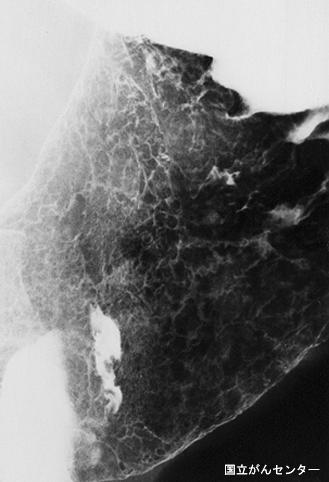

질환(병리주체)의 분류 악성 림프계종양/악성 림프종

부위(장기별) 위(부위)/2개 이상

검사방법 X-P

종양의 육안분류 0형(표재형)/IIc형(IIc)

종양의 최대경(밀리미터) 40이상

종양의 심달도 sm